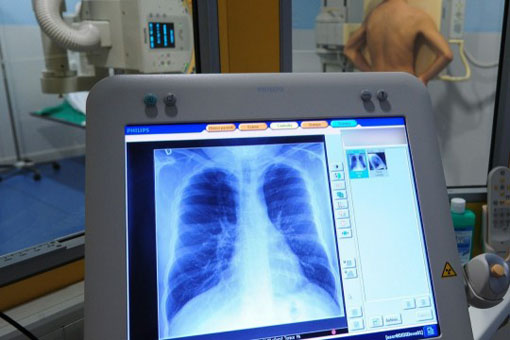

La proteina di fusione EML4-ALK codificata da tale gene rappresenta un importante bersaglio molecolare per la terapia del carcinoma polmonare non a piccole cellule (NSCLC) per il coinvolgimento di tale gene nello sviluppo tumorale.